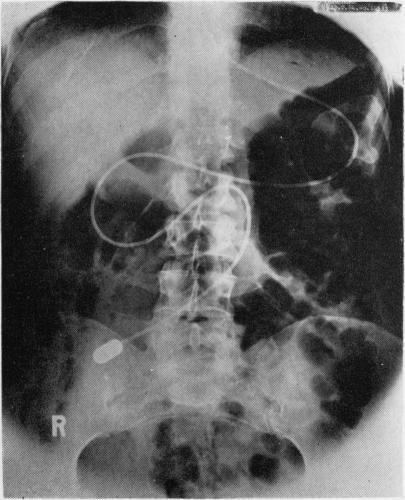

CROSBY SMALL-INTESTINAL CAPSULE WITH RADIO-OPAQUE TUBE AND LATEX SHEATH.